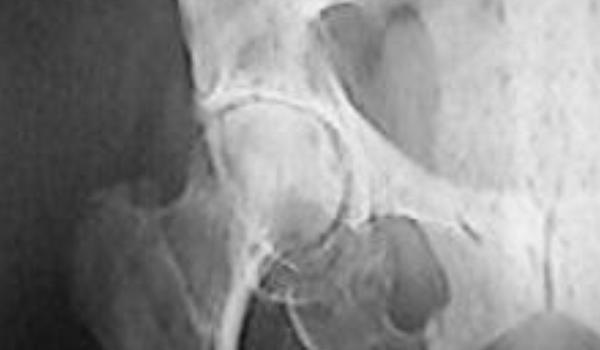

Buna ziua tuturor celor de pe acest site nu stiu cum sa incep mama mea are 68 de ani si a fost diagnosticata intr un final cu tomoare maligna vezica biliara tumoare maligna sant stang metastaze osoase iliace linfatice hepatice si nu mai stiu cate ca nu le mai retin numele deci cancer generalizat depasit oncologic de o saptamana de cand am aflat suntem in stare de soc nu ne revenim. Oasele cele mai frecvent atacate sunt cele ale coloanei vertebrale părții superioare a membrelor inferioare și osul pelvian. Cancerul de oase este cauzat de o problemă a celulelor care alcătuiesc osul. Această afecțiune poate conduce la fracturi și la dureri de os.